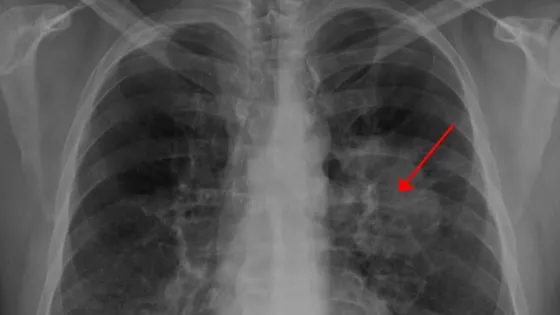

Обложка: Изображение из статьи. Рентгенограмма грудной клетки, демонстрирующая опухоль в легких / © James Heilman, MD, Wikipedia